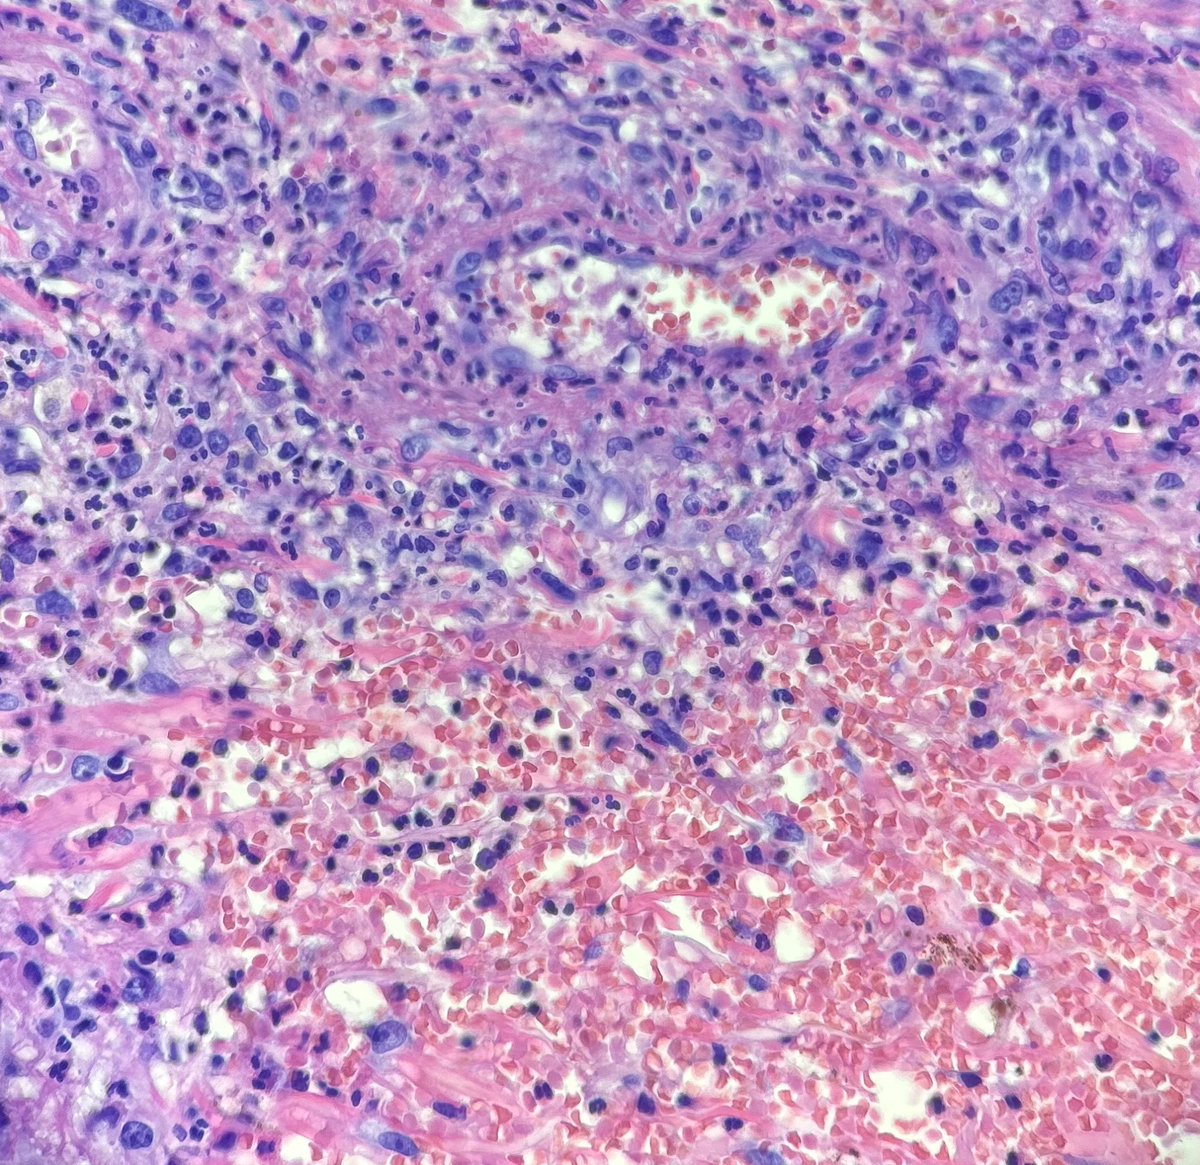

#dermpath #pathology #dermatology Recent case I had of cutaneous involvement by known granulomatosis with polyangiitis. These were photos I shared with the clinician who was concerned for infection.

Recent case I had of cutaneous involvement by known granulomatosis with polyangiitis. These were photos I shared with the clinician who was concerned for infection.